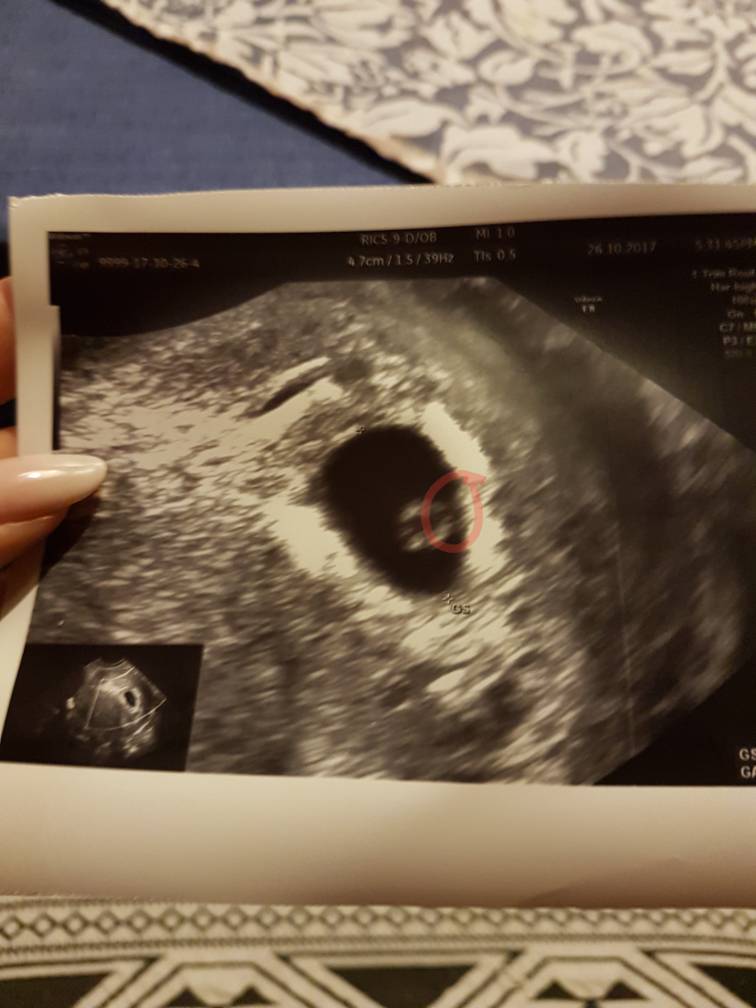

Ja wyraźnie widziałam jak załączenie "pulsowało", krew płynęła.

Serducha nie było

Tutaj dokładnie było widac jak krew pulsuje.. tak... ciężko mi opisac;p ale lekarz powiedział wyraźnie że na serducho za wcześnie

Z tego co mówił lekarz ok 6 już jest serce i słychać je wyraźnie.

U mnie nic nie było słychać i serca też nie było - tak powiedział lekarz.:p

Na monitorze widać pulsowanie kropki i to właśnie jest serduszko. Niektórzy nie słuchają serduszka do 8tc żeby nie szkodzić zarodkowi( jakieś badania ponoć są) ale można zobaczyc jakie ma tętno za pomocą motion mode [emoji6]